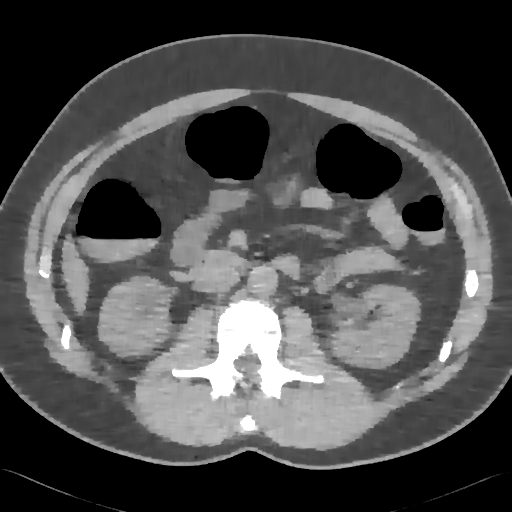

Elimination of noise in ultra low dose CT data

original section